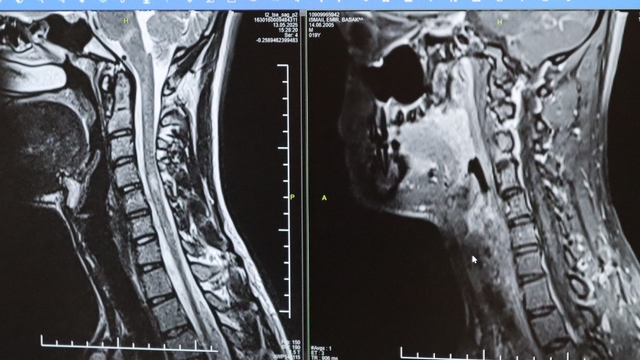

Kamışlı, 30 Mayıs Dünya MS Günü dolayısıyla yaptığı yazılı açıklamada, MS'in bağışıklık sisteminin sinir sistemine saldırmasıyla gelişen kronik bir hastalık olduğunu aktardı.

"Bunlar arasında görme bozukluğu, kol ve bacakta kuvvetsizlik, uyuşmalar, dengesizlik, yürüme bozukluğu, idrar problemleri veya aşırı yorgunluk ve halsizlik hali bulunmaktadır. MS ataklarla seyredebilir ve genellikle en sık görülen formu budur. Birdenbire bir şikayet ortaya çıkar ve zamanla azalır veya kaybolur. Bir de 'progresif' dediğimiz ilerleyici formu vardır. Bu ilerleyici formda hastalık yavaş yavaş ilerlemektedir. MS her hastada farklı seyreder. Bu nedenle tek tip MS hastalığından bahsetmek mümkün değil."

Hastalığın tanısı ne kadar erken konur ve tedaviye ne erken başlanırsa, hastaların günlük hayatta aktif ve üretken bir şekilde devam etmelerinin o kadar kolaylaştığını belirten Kamışlı, "Günümüzde MS'le ilgili çok fazla gelişme oldu ve tedavi seçenekleri arttı. MS merkezlerinde bu tedavi seçeneklerine ulaşmaları mümkün. Hastalarımız için doğru tanı, düzenli takip ve uygun tedavi oldukça önem teşkil etmektedir." ifadelerini kullandı.